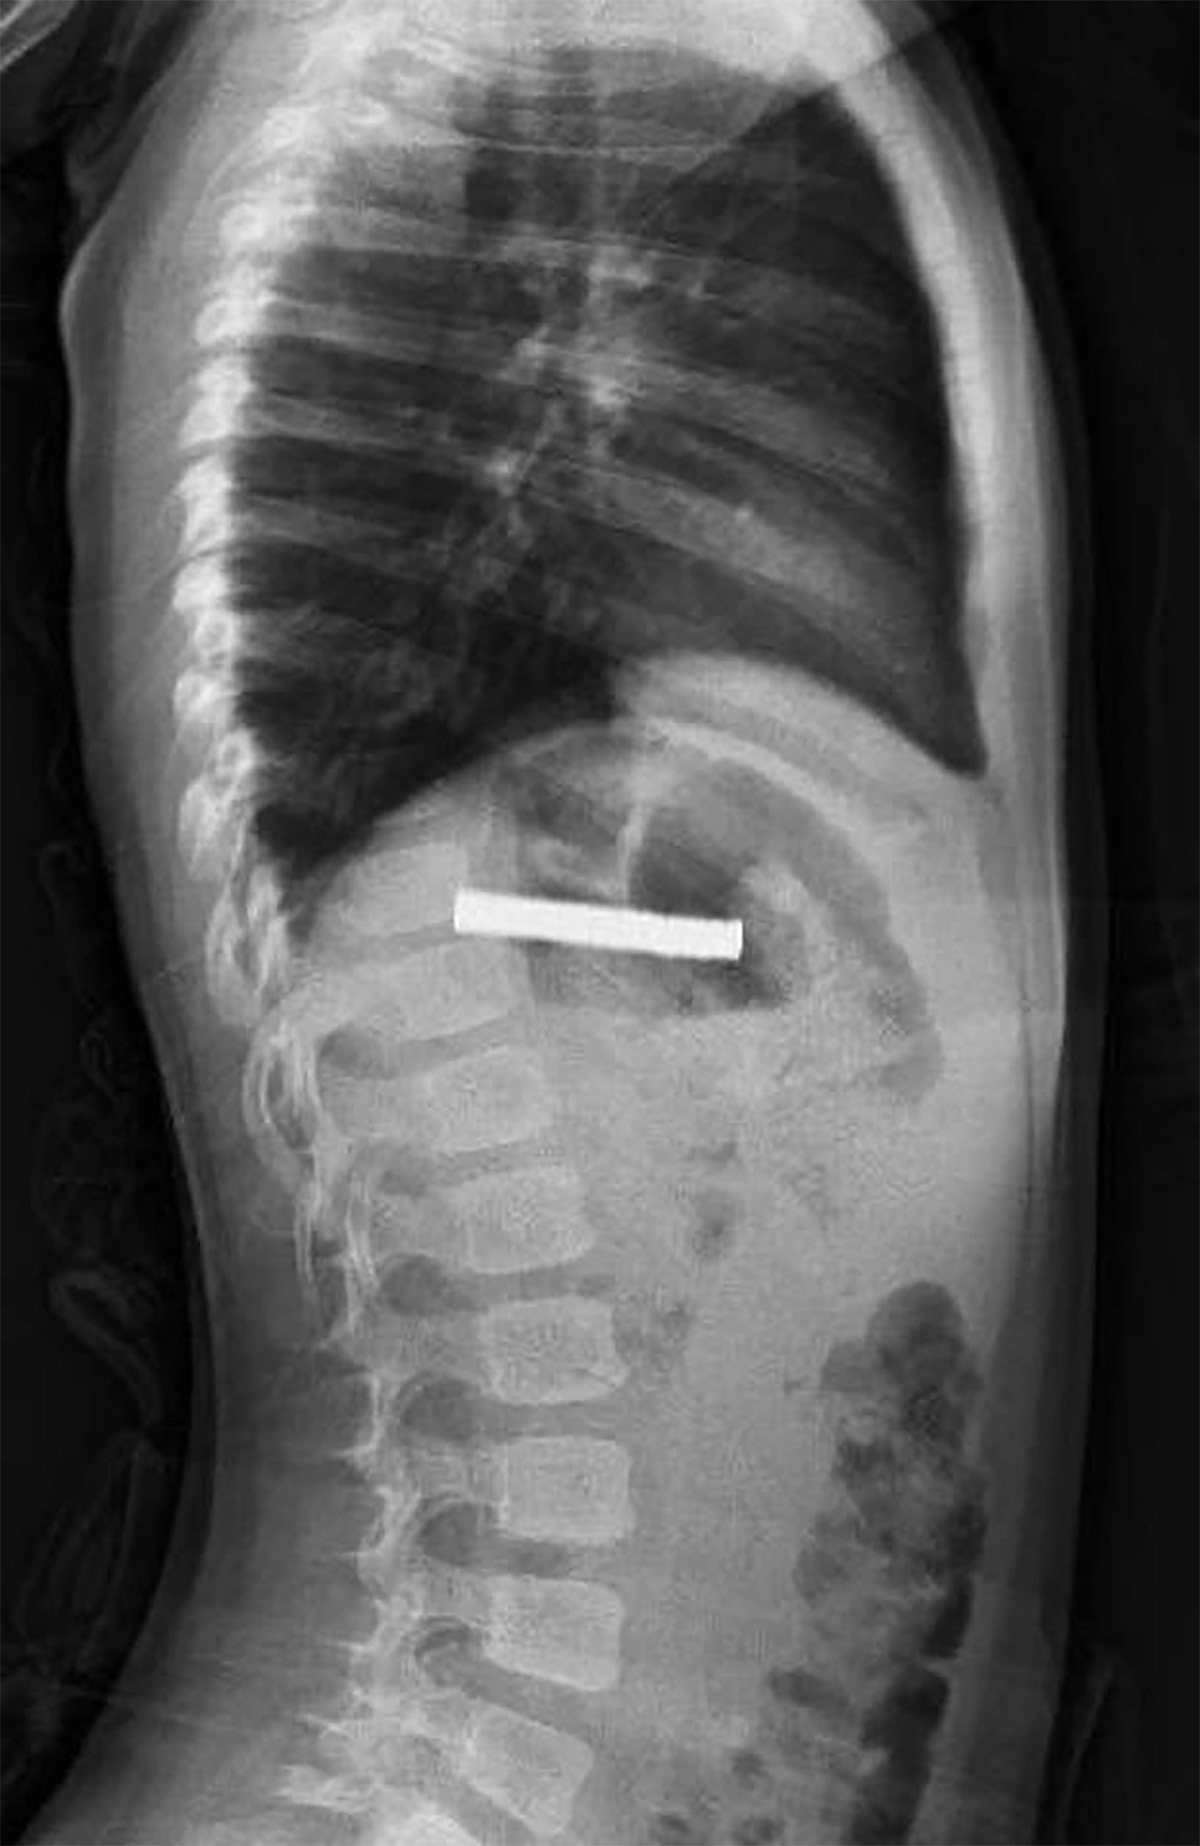

İlk müdahalenin ardından çocuk, ileri tedavi için Elazığ Fırat Üniversitesi Hastanesi’ne sevk edildi. Çocuk Gastroenteroloji Hepatoloji ve Beslenme Bilim Dalı Başkanı Prof. Dr. Yaşar Doğan tarafından yapılan endoskopik operasyonla, çocuğun yemek borusuna yapışmış 19 mıknatıs çıkarıldı.

Uzun süre yemek borusunda kalan mıknatısların, yemek borusu ve mide girişinde zedelenmeye yol açtığı, ancak yapılan müdahalenin ardından çocuğun sağlık durumunun iyi olduğu ve taburcu edildiği öğrenildi.